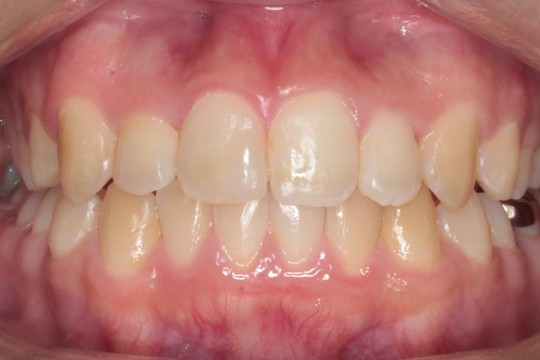

正面 治療後

調布市の20代男性

主訴:前歯のデコボコを直したい

使用装置:インビザライン

治療期間:約2年

治療費用:93.5万円(税込)

治療結果:叢生が改善されました

にもかかわらず今回は非抜歯矯正での対応となります

非抜歯矯正で十分に並べられるという確信の元で行っております